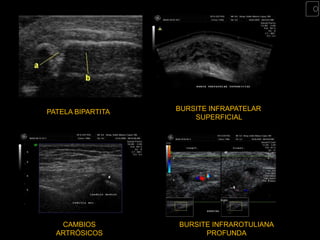

PATELA BIPARTITA   BURSITE INFRAPATELAR

SUPERFICIAL

CAMBIOS         BURSITE INFRAROTULIANA

ARTRÓSICOS             PROFUNDA

PATELA BIPARTITA BURSITE INFRAPATELAR SUPERFICIAL CAMBIOS BURSITE INFRAROTULIANA ARTRÓSICOS PROFUNDA